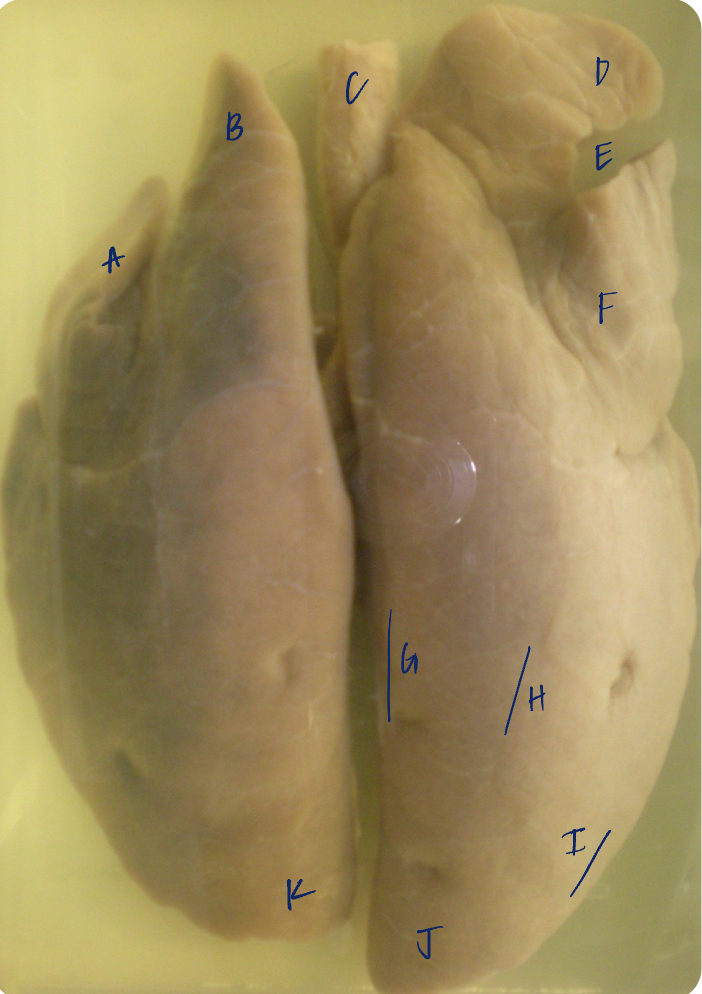

A

(pig lungs, dorsal)

L cranial lobe, caudal segment

B

(pig lungs, dorsal)

L cranial lobe, cranial segment

C

(pig lungs, dorsal)

trachea

D

(pig lungs, dorsal)

R cranial lobe

E

(pig lungs, dorsal)

cardiac notch

F

(pig lungs, dorsal)

middle lobe

G

(pig lungs, dorsal)

dorsal border

H

(pig lungs, dorsal)

costal surface

I

(pig lungs, dorsal)

basal border

J

(pig lungs, dorsal)

R caudal lobe

K

(pig lungs, dorsal)

L caudal lobe

A

(pig lungs, dorsal)

L cranial lobe, caudal segment

B

(pig lungs, dorsal)

L cranial lobe, cranial segment

C

(pig lungs, dorsal)

trachea

D

(pig lungs, dorsal)

R cranial lobe

E

(pig lungs, dorsal)

cardiac notch

F

(pig lungs, dorsal)

middle lobe

G

(pig lungs, dorsal)

dorsal border

H

(pig lungs, dorsal)

costal surface

I

(pig lungs, dorsal)

basal border

J

(pig lungs, dorsal)

R caudal lobe

K

(pig lungs, dorsal)

L caudal lobe